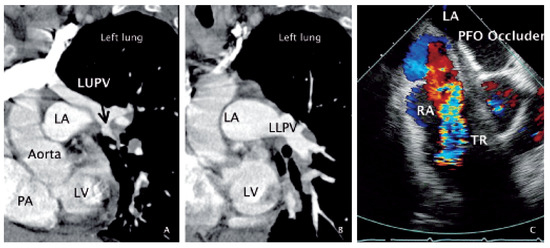

Anomalous Left Upper Pulmonary Vein Connection with Right Heart Failure Following Closure of Patent Foramen Ovale

by Christina Eigenmann and Christian Seiler

A68-year-old woman was admitted for rapidly progressive systemic sclerosis [...] Full article

Figure 1